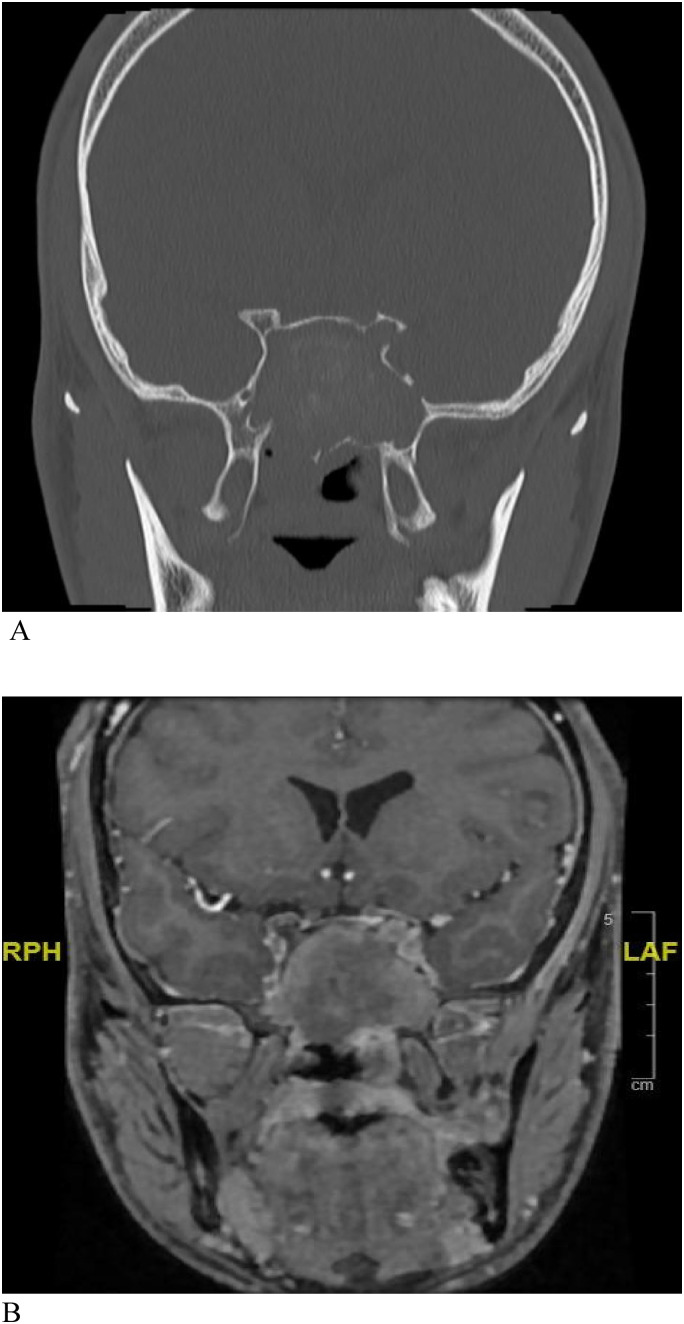

Allergic fungal rhinosinusitis (AFRS) is a subtype of chronic noninvasive sinusitis accounting for 7.8% (0.2%-26.7%) of all chronic rhinosinusitis cases. A definitive diagnosis is usually made after sinus surgery. Successful treatment requires a combination of surgical and medical management. Although orbital involvement is relatively common, reports on optic neuropathy and acute vision loss are limited. Herein, we present a series of 3 patients with AFRS who presented with acute visual loss as the chief complaint. All 3 patients were otherwise healthy adults in their early 20s with extensive nasal polyps on endoscopic nasal examination and bone erosion in the bilateral orbits and lateral wall of the sphenoid sinus on the affected side on imaging. One of the 3 patients had bilateral cranial nerve IV defects in addition to cranial nerve III defects. All patients underwent endoscopic sinus surgery with orbital decompression and were followed up postoperatively by both otolaryngology and ophthalmology services with endoscopic and radiologic evaluation. Unfortunately, no meaningful improvement in vision was observed in any patient despite successful nerve decompression. Prompt diagnosis and early medical and surgical intervention are warranted to prevent complications in patients with AFRS with orbital extension.

Abstract Image